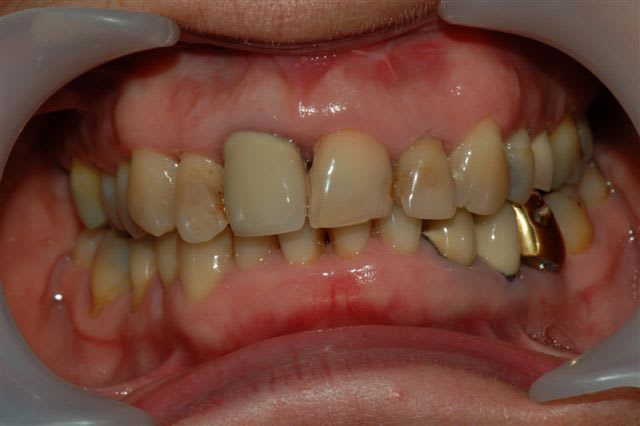

voici un cas traité en dentisterie globale à l'aide du laser en paro et du cerec en occluso, le cas à été terminé en 2010, cette semaine examen microbiologique de routine avec maintenance paro, il n'y a plus de flore pathologique dans la bouche de cette patiente

Emma

Reste plus qu'à faire des greffes de gencives secteur 4.

Tu as une radio zone 11-21, perte de papille importante.

salut ceramik, toujours aussi contente de te lire, tes désirs sont des ordres, radios faites en 2010, les photos dates de juin 2010, les papilles entre 11 et 21 sont entrain de se reconstruire petit à petit, au prochain contrôle de maintenance, je ferai des radios et des photos pour montrer l'évolution engendrée par la biostimulation laser diode.

Joli cas Emma, juste une remarque, le travail de l'espace inter incisif en jouant sur la convexité des profils d'émergence masquerait le manque immédiat de papille et à terme la papille se reconstruirait plus rapidement.

Il est vrai qu'au vu de la difficulté initiale du cas ce type de détail peut passer à la trappe.

très belle reconstruction par cfao directe!!!!!